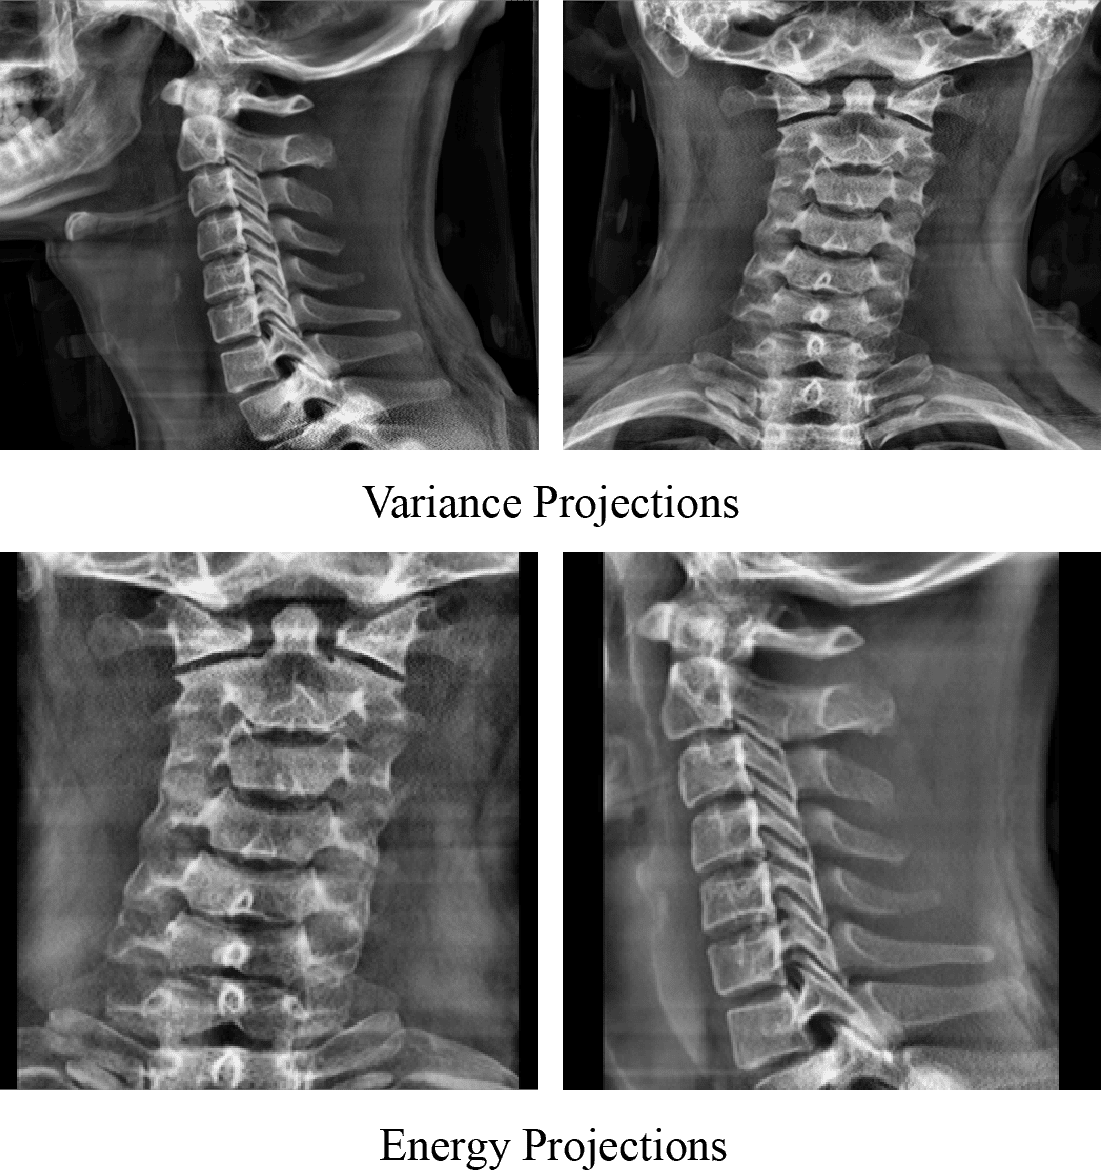

For vertebra segmentation, we employ the energy projection(Haralick et al., 2007), defined as:

Peng(x,y)=z=1ZI(x,y,z)2P_{\text{eng}}(x,y)=\sum_{z=1}^{Z}{I(x,y,z)^{2}} (2)

Energy projection amplifies high-intensity anatomical structures, such as cortical bone, and enhances vertebral boundaries that are critical for accurate segmentation. This property is especially beneficial when generating projection-based representations for multi-label vertebra segmentation under anatomical overlap. Representative examples of variance and energy projections derived from the same cervical spine CT volume are shown in Figure 3, illustrating their complementary characteristics for ROI localization and vertebra segmentation, respectively. Comprehensive description of alternative projection operators, including their mathematical formulations and visual comparisons, are provided in the Supplementary Section S3.

CT volumes in the RSNA dataset exhibit substantial variability in the number of axial slices per patient, ranging from fewer than 200 to more than 500 slices. For scans with sparse sampling, vertebral structures may be underrepresented in projection space, negatively affecting downstream localization and segmentation performance. To mitigate this issue and ensure consistent volumetric resolution across patients, we apply slice interpolation as a preprocessing step.

CT volumes were interpolated using cubic spline interpolation (Aja-Fernández et al., 2024) to preserve anatomical continuity and reduce high-frequency artifacts, while segmentation masks were interpolated using nearest-neighbor interpolation to maintain label integrity. After interpolation, all volumes contained at least 400 slices, ensuring comparable anatomical coverage across the dataset. Figure 4 demonstrates an example of the projection with and without interpolation for the CT volume and its corresponding mask. It is clearly observed that the projection with the interpolation showed more distinct vertebra features. Hence, this preprocessing step improved the clarity and structural consistency of projection-based representations, particularly for low-slice scans.